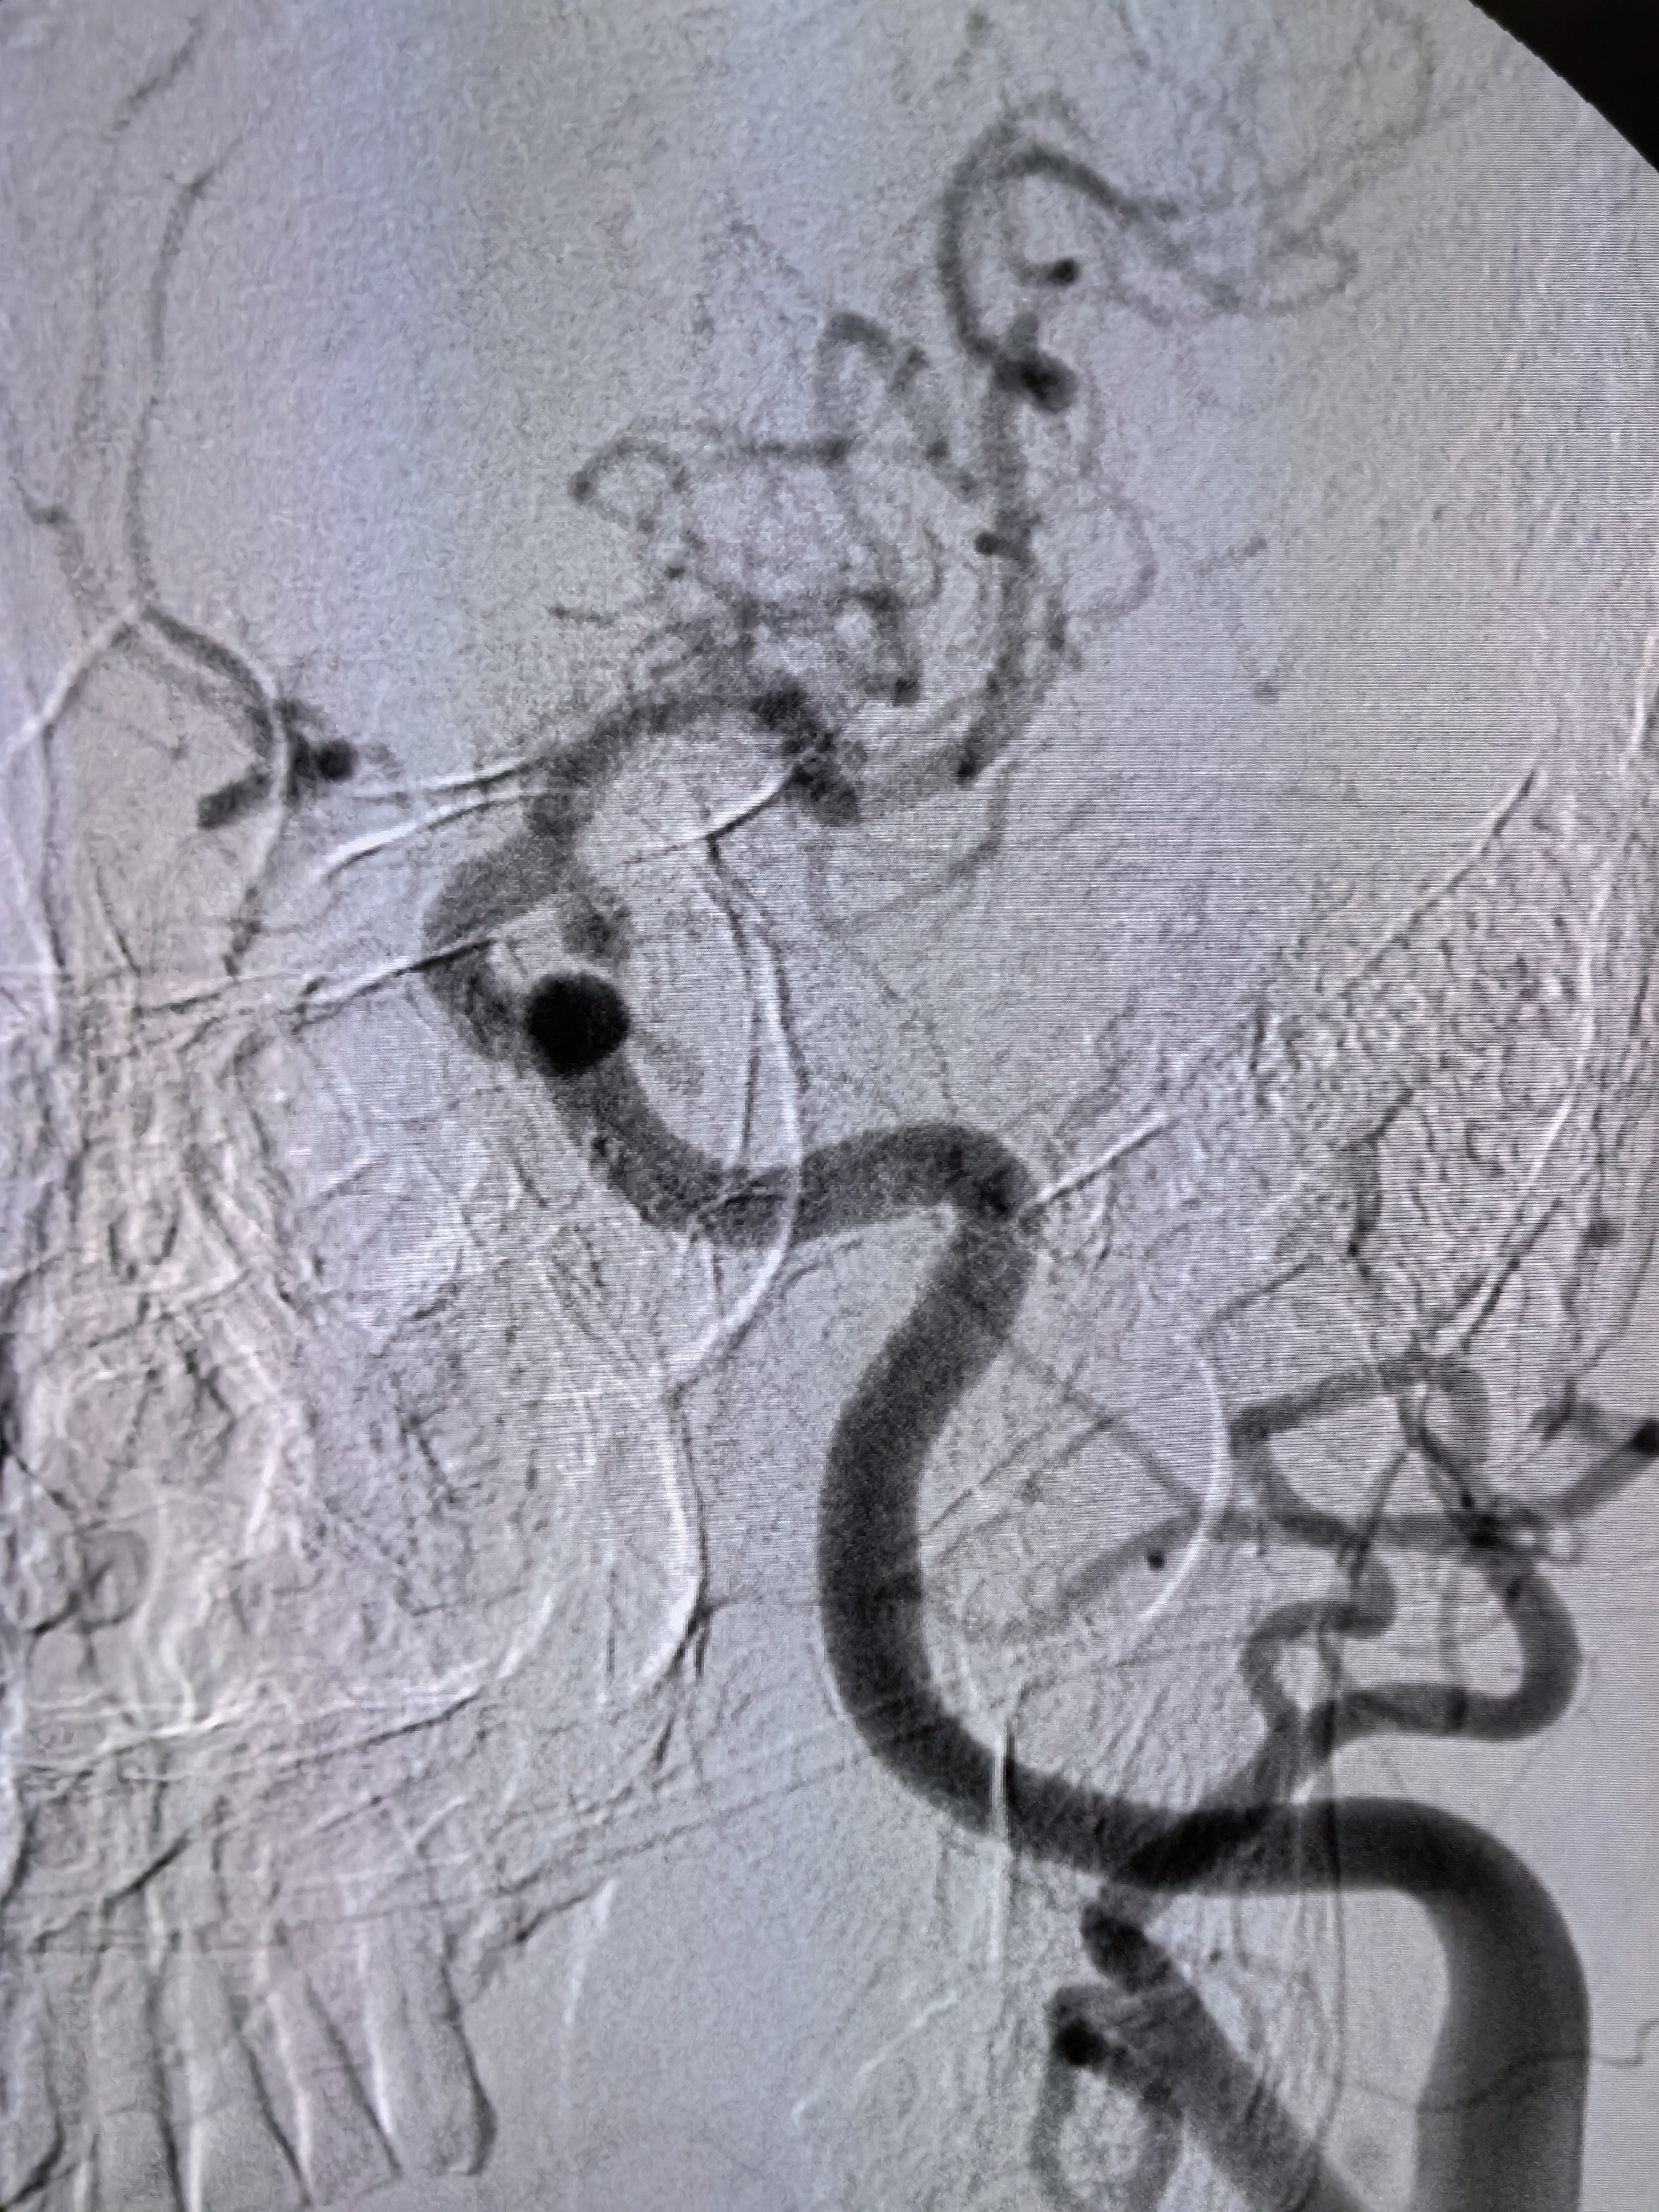

患者ZDY,男性,85岁,突发意识障碍,左侧肢体活动不灵5小时入院。既往房颤,胸腔积液,脑梗死病史多年。患者缘于5小时前突发意识障碍,伴左侧肢体活动不灵,家属发现以后急诊送入院。查体:血压140/90mmHg,房颤节律。浅昏迷,双眼向右侧凝视,余颅神经查体不配合。左侧肢体肌力0级,右侧肌力5级,左侧病理征(+)。NIHSS评分12分。

1、本例患者高龄男性,既往房颤病史,突发意识障碍伴左侧肢体无力,符合大血管病变,具备介入治疗指征。

2、患者高龄,3型弓,颅内血管迂曲,颈内动脉末端闭塞,血栓符合较大,SWIM技术完成取栓。